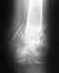

Здравствуйте! Прошло 15лет, у меня была травма ноги. Нога меня не беспокоит не болит только дефект видно. Врач поставил мне диагноз энхондрома левой б/б кости. Врач говорит, что операция будит сложная, будут резать кость и потом восстанавливаться надо больше года. Скажите, пожалуйста, есть ли другой способ удаление этого хряща. Спасибо.Во мои снимки.http://s47.radikal.ru/i118/1105/11/eefec2497869.jpghttp://s41.radikal.ru/i093/1105/dc/3ec1b497c732.jpg